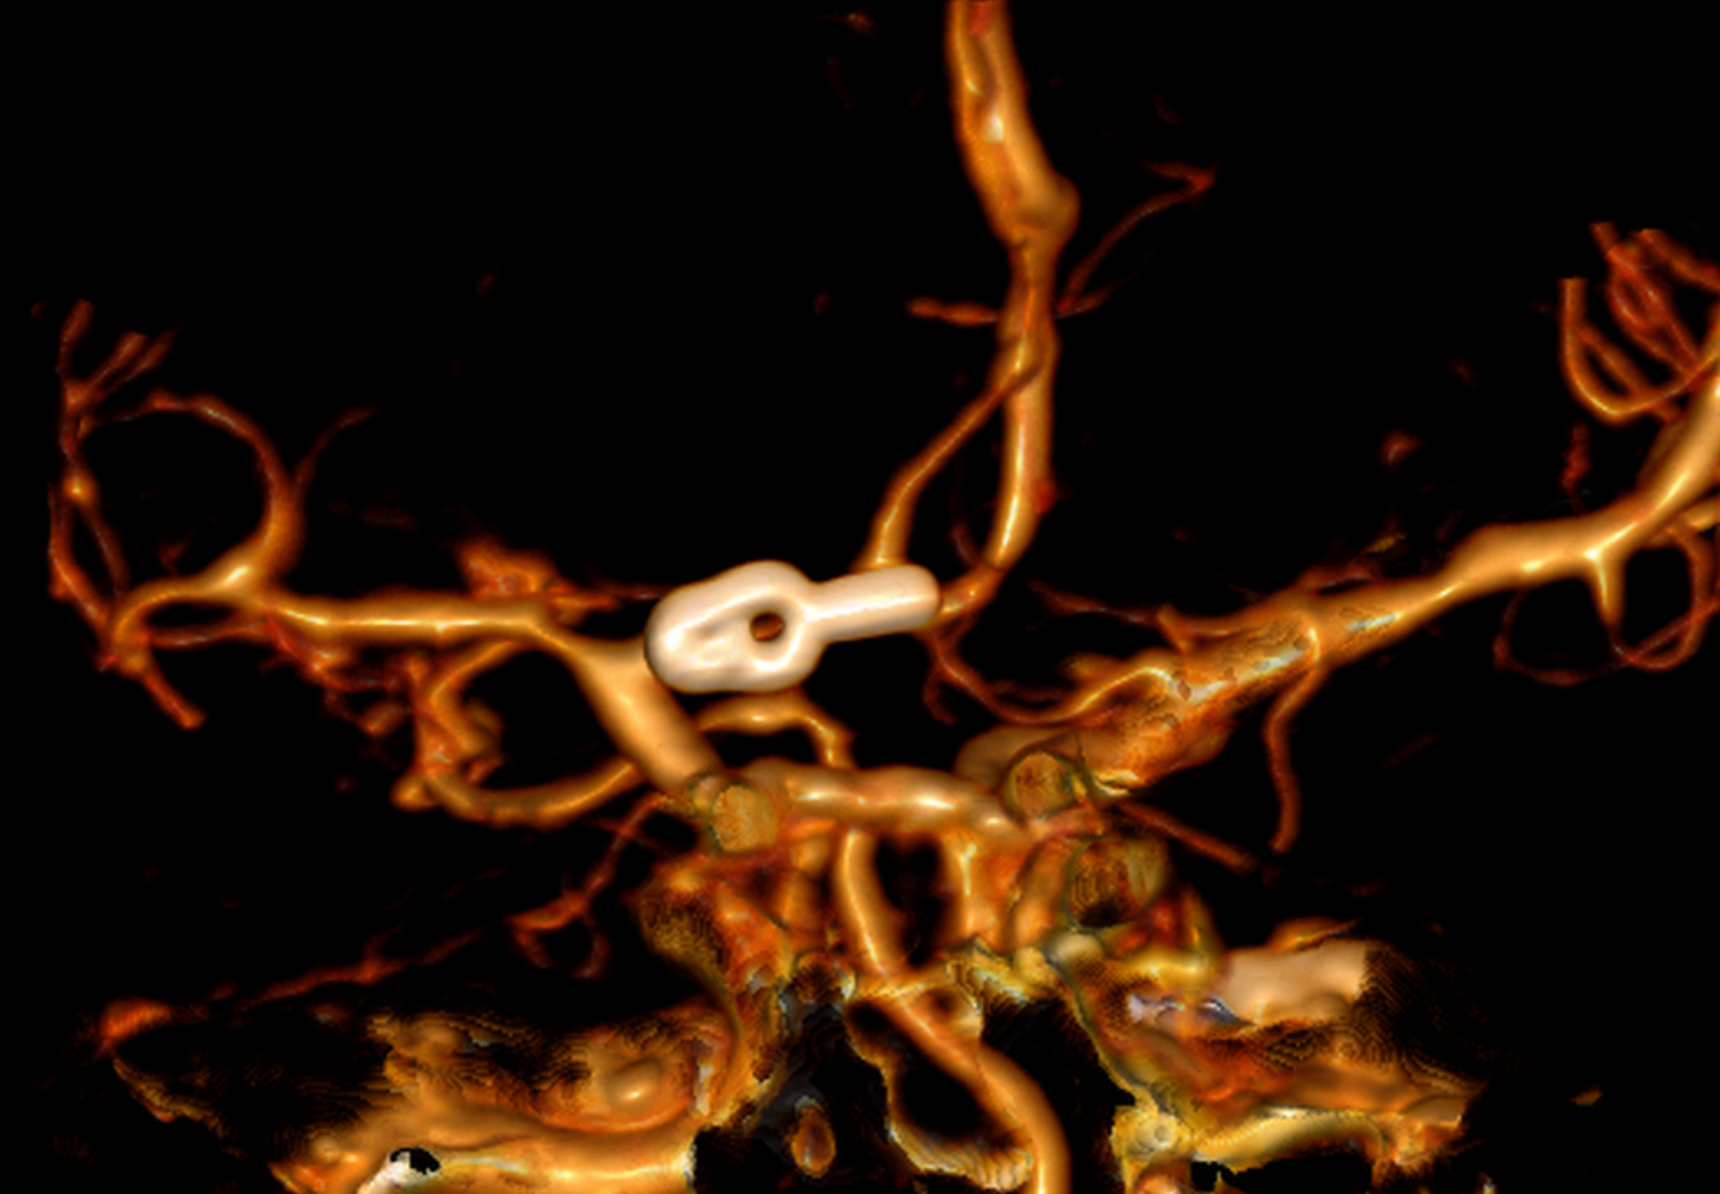

Aneurisma recurrente visto cerca de clips

Angiografía cerebral 3D que muestra un aneurisma